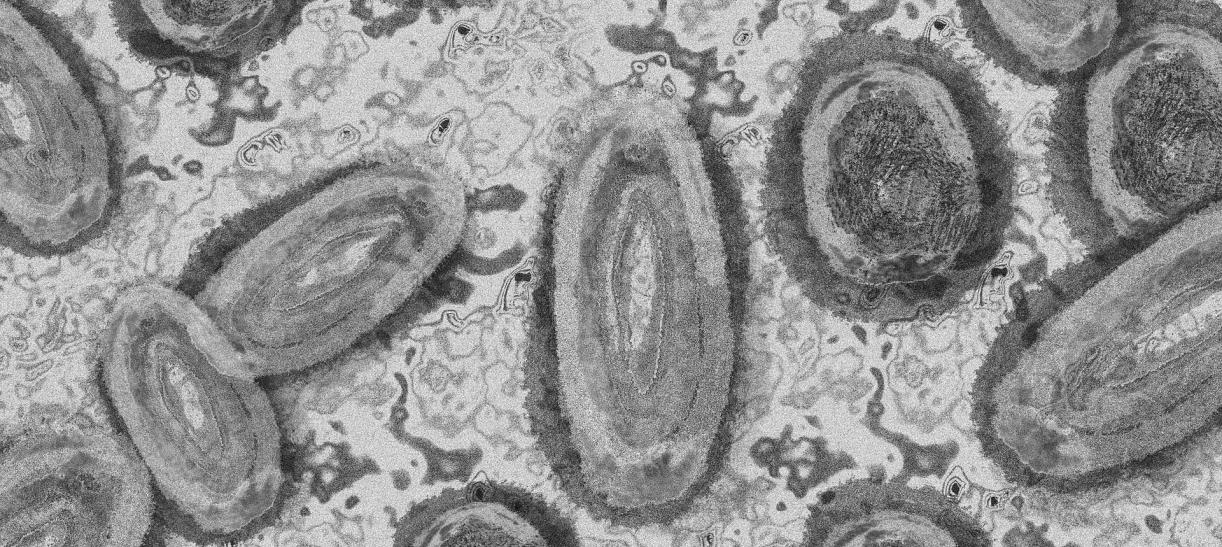

Siguen en aumento los casos de viruela símica en Colombia

El Instituto Nacional de Salud (INS) informó vía web sobre los casos de viruela símica confirmados en el país.